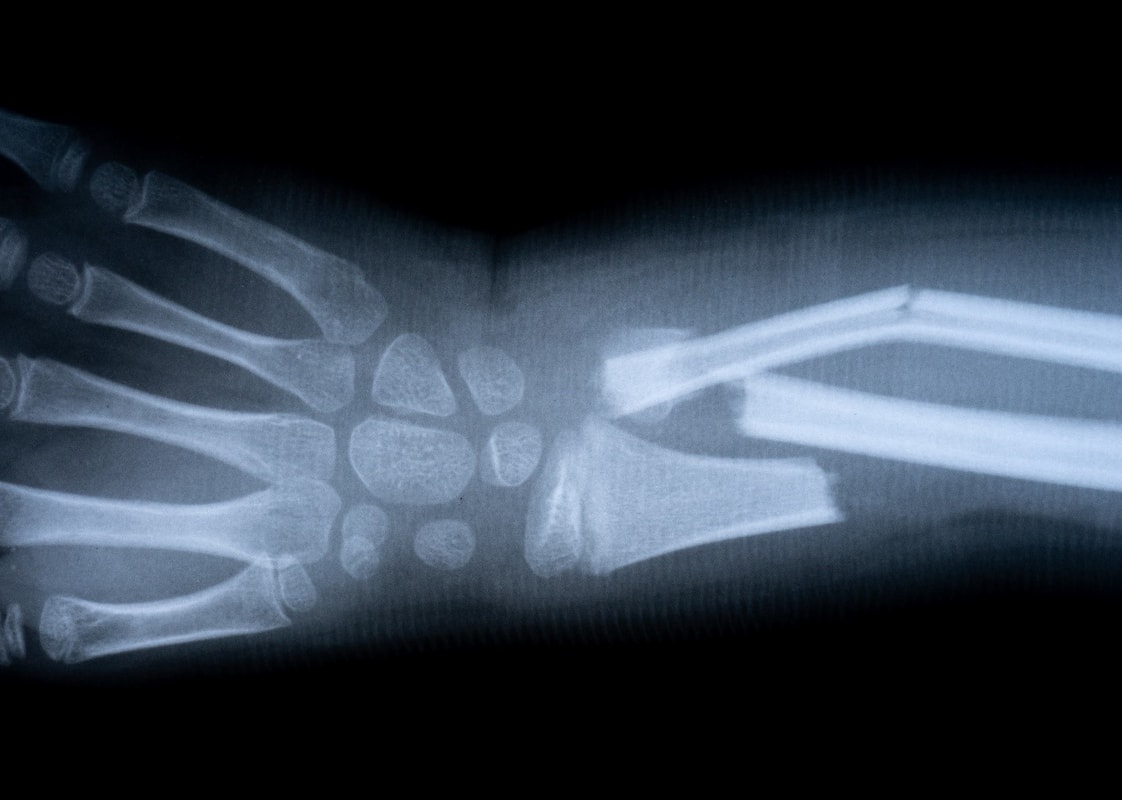

Fractures of wrist, hand bones and fingers

The wrist usually breaks when an individual falls on the outstretched fist.

Fractures of the bones of the fist can be the result of direct impact or bruising. They are accompanied by swelling, pain, unnatural appearance, impaired function, and sometimes an open wound. The fist should be immobilized on a straight splint and a lump of cloth or bandage should be inserted into the fist cavity.

The fractured joint should not be "pulled" but immobilized. If severe pain is present, analgesics should be given. The injured fist should be lifted up to reduce bleeding and swelling. Hand bleeding should be handled in the usual way.

The forearm is attached to the splint with a bandage.